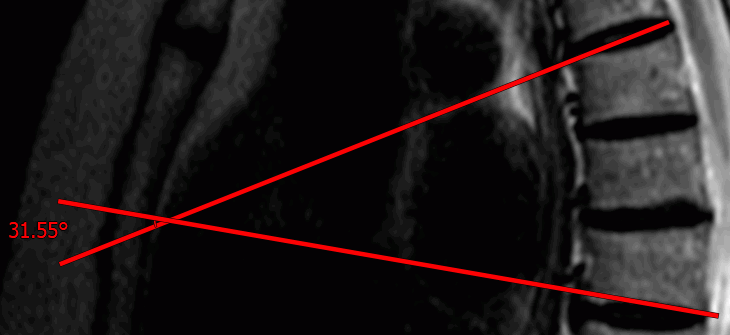

2.19.5 Cobb angle meter

To measure a Cobb angle:

1. Activate the Cobb angle PIC tool from the toolbar by clicking the left/right/middle mouse button. To continue work with this tool, use the button with which the tool was activated. To learn more about tool control, see Section 1.14.

2. Draw a line that runs along the border of one of the vertebrae. To do this, click the mouse button to set two points through which the line must pass.

3. Likewise, construct a line for the second vertebra.

4. To cancel an incomplete measurement, press Esc.

To display additional parameters, hover the mouse over the measurement tool or the measurement value. Right-click the mouse and select the Tool options... item from the context menu.

In the Tool options dialog box, provide the measurement name, as well as the color, the line width, and the font size for the angle value. To join the measurement value to the angle with a dashed line, check the Footnote line box.

To display the value of the adjacent angle, check the Adjacent angle box.

To show the angle value at the intersection of segments, check the Show intersection box. If this function is disabled or the segments do not intersect, the angle value is shown only at the intersection of normals. In Fig. 2.30 the option Show intersection is disabled, and in Fig. 2.31 is enabled.

To use these parameters by default, check the box Set as default.

To apply the settings, click OK. To cancel, click CANCEL.

To delete mesurement, locate the cursor on it, right-click the mouse and select the Remove object. For more information see Section 2.19.12.

This tool is also available from the image context menu and from the Image main menu item. Activation is only possible with the left mouse button.

The measurement results are not saved in the project file. To save the measurement results, export the current image to a file (see Section 2.28) or use polygonal marker lines (see Section 5.12.4).